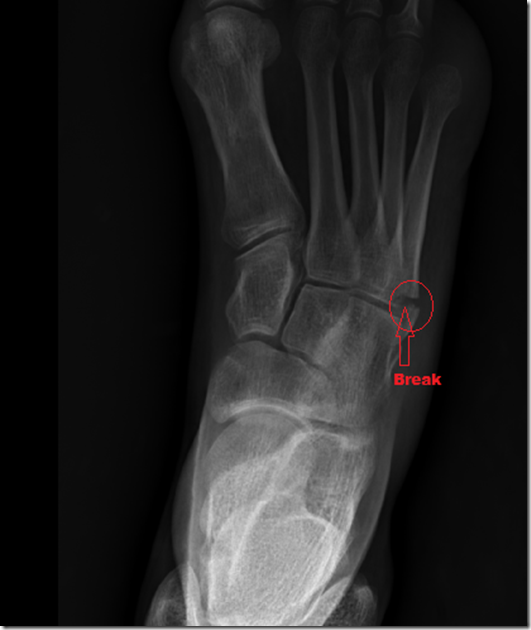

Around 9:30 AM, we sent the kids over to the neighbors, while my wife took me to the ER. Behold the resulting picture, in which I have clearly labeled a fracture in my 5th metatarsal.

I now have a boot on my foot that weighs a ton, and am trying to keep the foot iced and elevated as much as possible. I have to talk to an orthopedic surgeon on Monday to see if I need surgery. The gap between the bones may be significant enough to require a pin to hold it together. Either way, I’m probably looking at 6-8 weeks to heal.